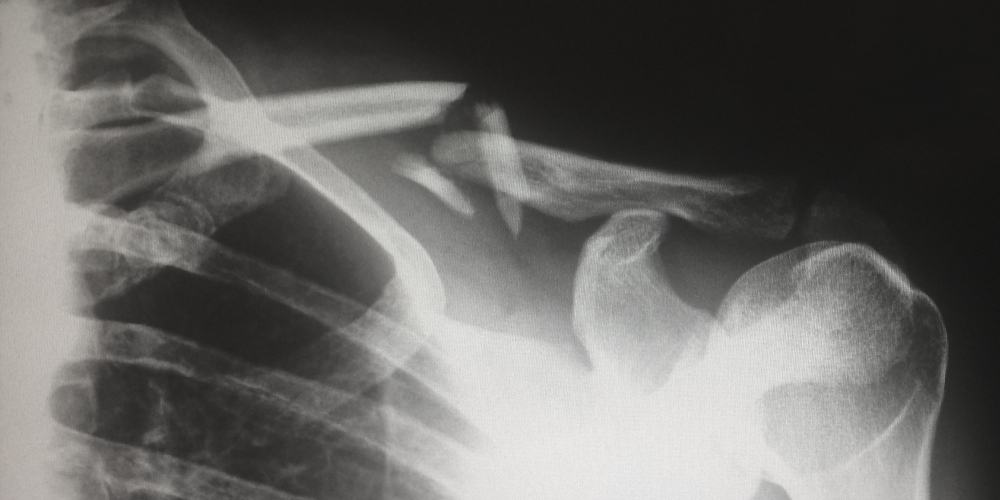

Jednym z wymienionych przeze mnie sytuacji kryzysowych są kontuzje. Wiele osób, które poznałem na siłowni wyznawało filozofię „weź tabletki i ćwicz dalej”. Dzisiaj wiem, że to poważny błąd. Zawsze w czasie treningu słuchaj swojego ciała – na pewno poczujesz, jeśli coś będzie nie tak. Przez to, że przez jakiś czas sam tak nie robiłem, teraz po kilku godzinach marszu moje kolana i kostki są w opłakanym stanie. Jeśli tylko czujesz, że coś zaczyna być z Twoimi stawami (zwykle, bo one się rozwijają wolniej, niż mięśnie) lub mięśniami nie tak – poluzuj trening i zasięgnij rady. Jeśli jest taka potrzeba – skorzystaj z rehabilitacji. W ujęciu długoterminowym pozwoli Ci to uzyskać lepsze efekty. Trening z zaogniającą się kontuzją lub w czasie choroby zwykle spowoduje tylko, że będziesz musiał na dłużej zrezygnować z ćwiczeń. A wtedy i Twoje cele oddalają się w czasie, i ciężej będzie Ci wrócić do ćwiczenia po przerwie.

Z kontuzjami jest też związana pewna filozofia treningu operatorów: trening nie ma Cię zajechać do upadłego, tylko przygotować Twoje ciało na wielkie wyzwania. Dlatego w Wojskach Specjalnych duży nacisk jest postawiony na zapobiegnie kontuzjom, ich wykrywaniu i leczeniu. Trening ma sprawdzić ciało operatora i przygotować je, żeby w każdej chwili było gotowe stanąć do walki.

Podstawowa różnica pomiędzy operatorem a maratończykiem jest taka, że maratończyk przygotowuje się do startu o odpowiedniej porze. Zna datę zawodów i pod nią ustawia plan treningu i regeneracji, posiłki i całe swoje życie. Operator musi być ciągle gotowy do akcji Jeśli rozkaz przyjdzie na pół godziny przed zakończeniem całego dnia ćwiczeń, jeśli właśnie jest po godzinie wyczerpujących ćwiczeń, musi być gotowy do przejścia kilkudziesięciu kilometrów lub przetrwania kilku dni na terenie wroga. Dlatego trening, nawet najcięższy, ma go przygotować do poddania ciała jeszcze większym obciążeniom. A kontuje, jeśli się pojawią, muszą być natychmiastowo wykryte i leczone, żeby ciało operatora mogło jak najszybciej być gotowe do takiej służby.